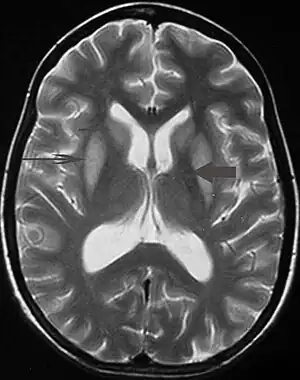

Tremor pode ser um sintoma associado a distúrbios nas partes do cérebro que controlam os músculos de todo o corpo ou em áreas específicas, tais como as mãos. Dentre os problemas neurológicos que podem produzir tremor incluem-se: hipertireoidismo, esclerose múltipla, acidente vascular cerebral, traumatismo craniano, doença renal crônica, doenças neurodegenerativas que danificam ou destroem partes do tronco cerebral ou o do cerebelo, sendo a doença de Parkinson o mais frequentemente associados com tremor. Transtornos neurológicos que causem tremor são chamados de parkinsonismo.